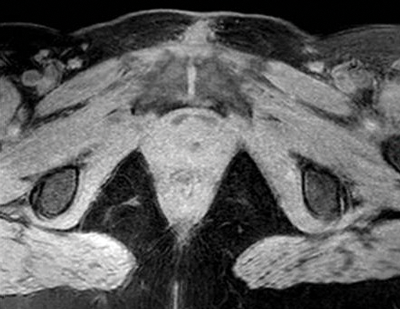

Figure 3a: Axial T1 fat sat pre gad - the urethral diverticulum cannot be seen.

Figure 3b: Axial T1 fat sat post gad showing low signal diverticulum

but no enhancement to suggest a tumour.

Figure 3c: Axial T2 fat sat shows debris within the divertiuclum.

Uretheral diverticula are usually characterised as a hyperintense periurethral cystic lesion on T2 weighted imaging (Figure 3). They are hypointense on T1 weighted sequences. The diverticula neck may or may not be visualised. The addition of a gadolinium-based contrast agent can help in differentiating diagnoses. Irregular enhancement or mass-like components within a diverticulum may suggest infection or malignancy [2]. Once identified, radiologists should report the size and number of urethral diverticula, as well as the presence of any complications. The position of the diverticular neck if visible should also be commented upon to aid possible surgical intervention [2].